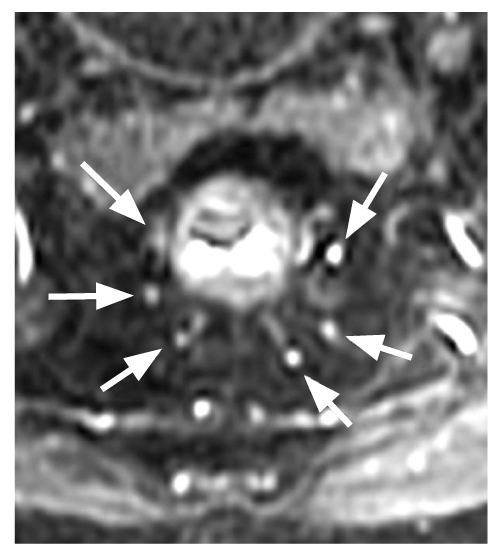

Во всех случаях, пригодных для интерпретации, определялось по 6 терминальных ветвей верхней прямокишечной артерии, локализованных на 1, 3, 5, 7, 9 и 11 часах условного циферблата (рис. 2). Следует отметить большое (7) число выявленных анатомических вариантов ветвления верхней прямокишечной артерии и способа достижения стенки прямой кишки (рис. 3, табл. 1). При этом на классический вариант ветвления верхней прямокишечной артерии на 3 ветви с последующей бифуркацией каждой приходилось 54% случая (на рис. 3 это, соответственно, 1, 5 и 6-й варианты); рис. 4, 5.

Рис. 2. Магнитно-резонансная томография: визуализировано 6 терминальных ветвей верхней прямокишечной артерии, локализованных на 1, 3, 5, 7, 9 и 11 часах условного циферблата.